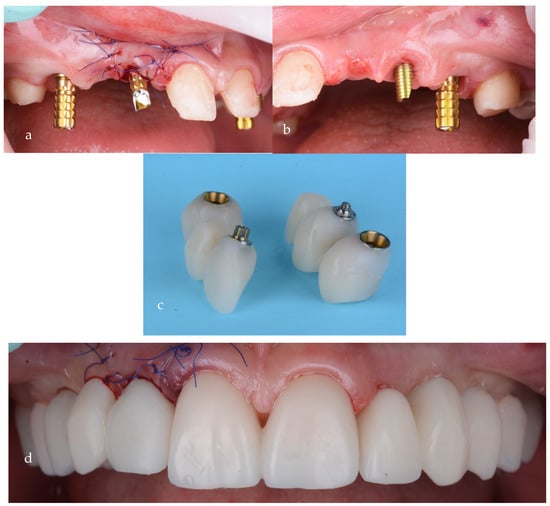

Two separate surgical procedures were planned. The first implant insertion surgery was performed for the upper jaw; four MIS V3 (MIS Implants Technologies UK Ltd., London, UK, implants were inserted in the position of 12, 14, 23 and 24, with two MIS Connect abutments (MIS Implants Technologies Ltd., London, UK) on 12 and 13 and two angulated multiunits on 14 and 24. To restore the patient’s esthetics, a temporary PMMA (Dentsply Sirona, Charlotte, NC, USA) bridge was used for the upper arch. After the implant placement, a period of 6 months of healing was decided.

Temporary screw-retained bridges, with proper emergence profiles, were used at this stage for soft tissue shaping of the gingival contour (Figure 15a–d).

Figure 15.

Screw-retained provisional bridges on temporary abutments: (a) first quadrant, (b) second quadrant, (c) provisionals and (d) after intraoral cementation.

After 3 more months of healing, the proper shaping of the tissue could be observed (Figure 16a,b). At this stage, an impression for the prosthetic restorations was taken (Figure 17a,b).